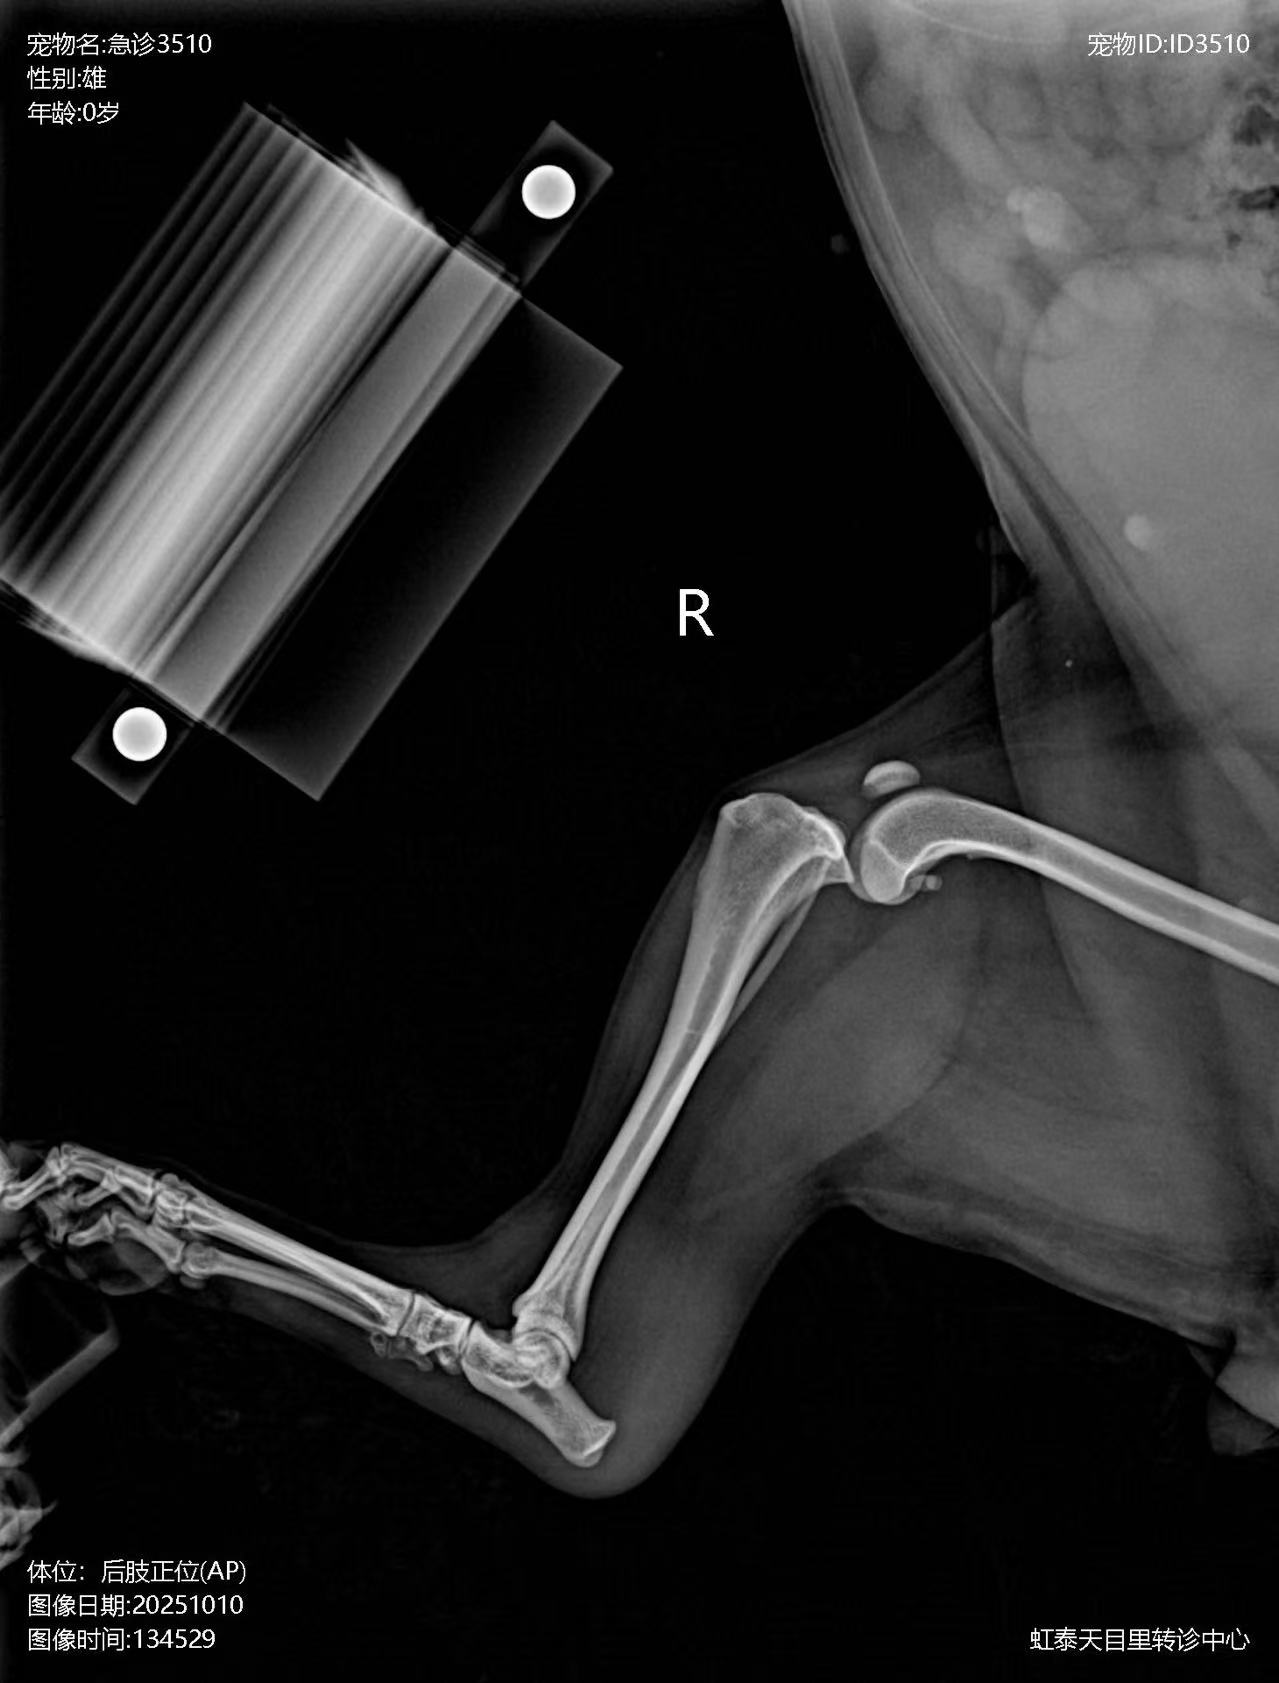

Preoperative X-ray: